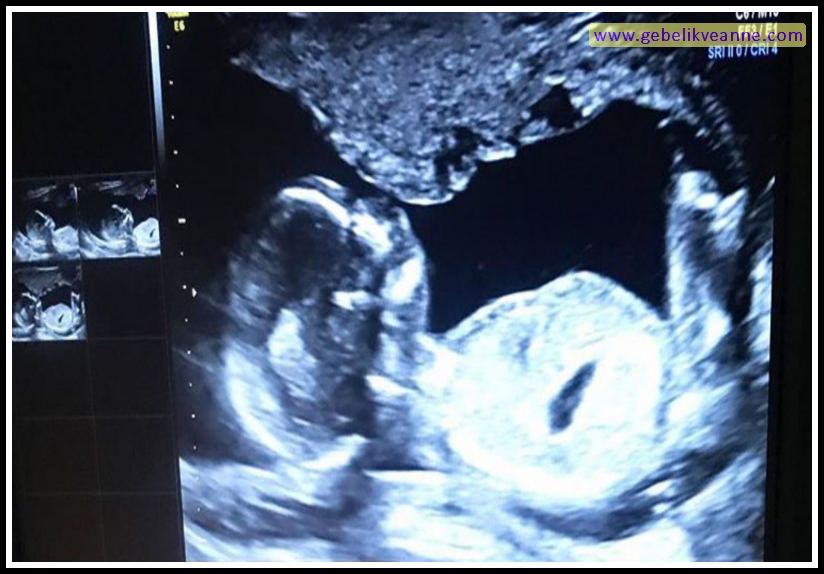

Bu yazımızda, bebeğin rahim içinde bu hafta nasıl geliştiğini, vücudunuzda olması muhtemel değişiklikleri ve almanız gereken bakımı açıklıyoruz. 17 haftalık gebelik görüntüsü incelendiğinde bebeğin boyunun önceki haftanın neredeyse iki katı olduğu görülür. Hamileliğin gelişme süreci hızlı bir şekilde devam ederken anne adayının en merak ettiği konu bebeğin ultrason görüntüsüdür.

Hamileliğinizin bu haftasında ter bezleri çok gelişmiş ve tamamen işlevsel olduğundan terleme şikayetiniz artacaktır. Hamileliğin gelişme süreci hızlı bir şekilde devam ederken anne adayının en merak ettiği konu bebeğin ultrason görüntüsüdür. 17 haftalık bebek nasıl görünür?